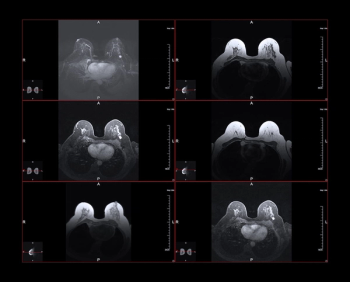

For women with dense breasts, the combination of mammography and supplemental breast ultrasound had a 36.4 percent higher sensitivity rate for detecting breast cancer in comparison to the combination of mammography and adjunctive AI, according to a new study.